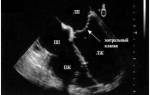

При УЗИ врач увидит следующие признаки:

- наличие тонких и плотных линейных структур и образований, которые не имеют связи с атриовентрикулярным клапаном;

- усиление эхоплотности мышечной ткани в местах прикрепления хорды, обусловленное локальной гипертрофией миокарда;

- ускорение кровотока в лишней хорде, выявляемое при допплерометрии.